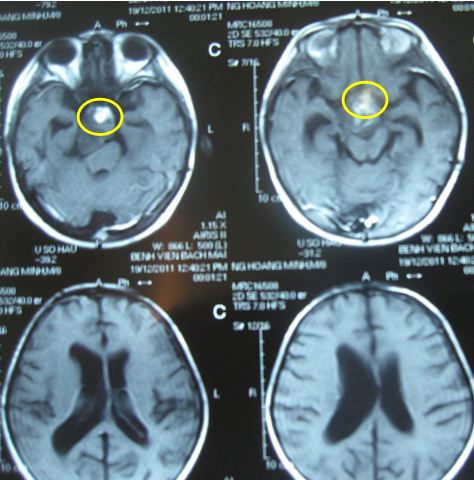

Trước điều trị: Hình ảnh chụp cộng hưởng từ (MRI) sọ não: là u sọ hầu (Vùng tổn thương trong vòng màu vàng; Vùng dãn não thất trong vòng màu xanh nhạt)

Sau xạ trị gia tốc 3 tuần (đợt 1): Hình ảnh chụp cộng hưởng từ (MRI) sọ não:kích thước u thu nhỏ lại rất nhiều (trong vòng màu vàng)